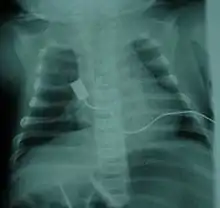

X-ray showing bell-shaped torso due to atrophy of intercostal muscles and using abdominal muscles to breathe. Bell-shaped torso is not specific to individuals with SMA

• Bell-shaped torso (caused by using only abdominal muscles for respiration) in severe SMA type 1[7]